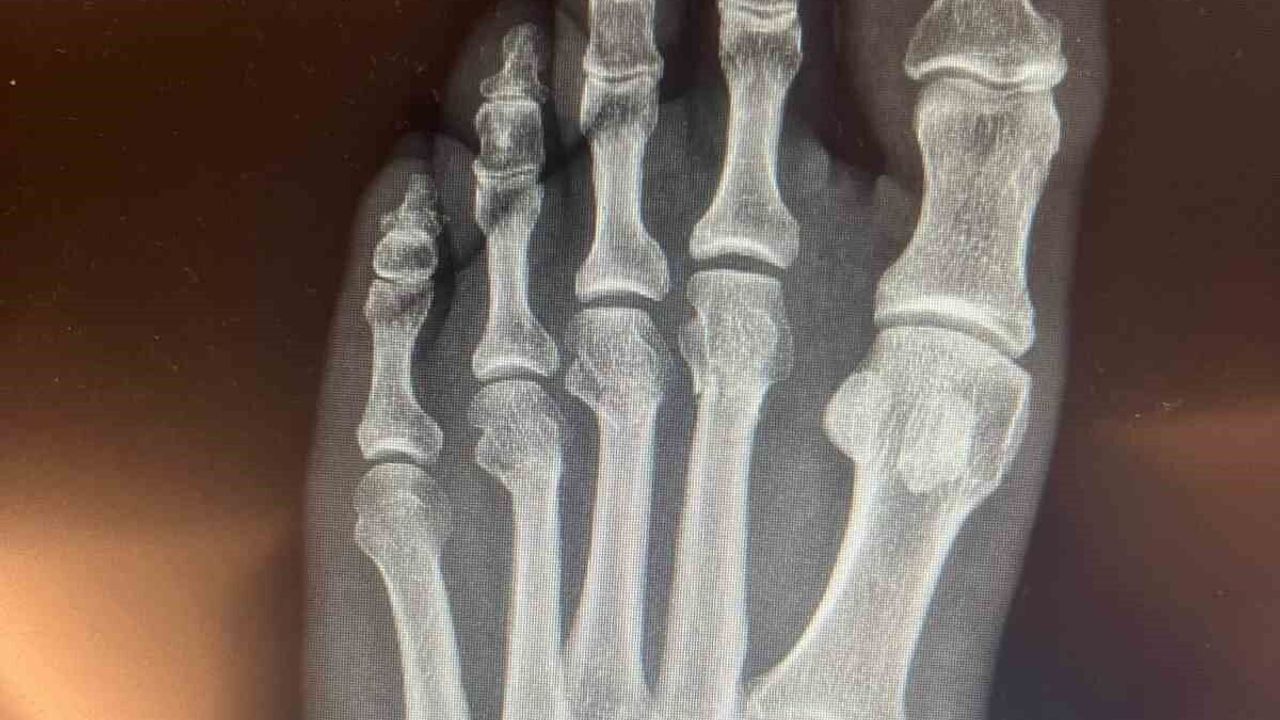

CHP Grup Başkanvekili Ali Mahir Başarır, geçen hafta TBMM’deki özel oturum öncesi gazetecilere yaptığı açıklamada, CHP Genel Başkanı Özgür Özel’in evde geçirdiği kaza sonucu ayağında ufak çaplı kırılma olduğunu duyurmuştu. Özel’in ayağında oluşan kırık hakkında sosyal medyada, Özel’in ‘ayağından vurulduğu’ iddiaları yer almıştı. Özel, tartışmalara ilişkin ayağının röntgen filmlerini paylaştı.